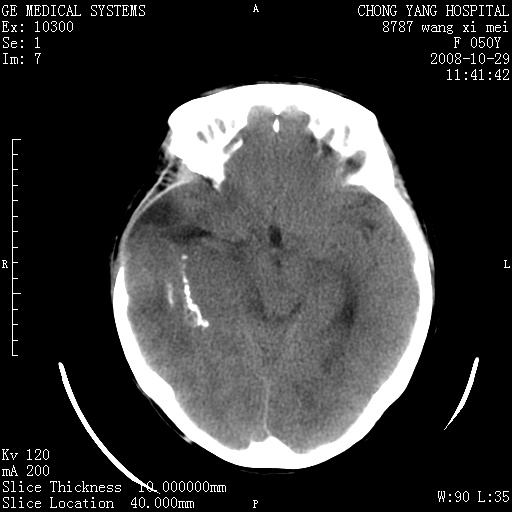

标题: CT16469:女,50岁,胶质瘤术后6年,今平扫加增强,请大家帮 [打印本页]

标题: CT16469:女,50岁,胶质瘤术后6年,今平扫加增强,请大家帮

右颞骨局限性缺如,局部脑组织无外隆。右颞叶可见片状脑脊液样低密度影,边缘较清,右侧侧脑室三角区可见一块状等密度影,且伴有强化,余未见明显异常改变。

考虑:右大脑术后改变伴肿瘤复发。

手术后局部片状低密度改变(软化灶),其后方颞叶似等密度病灶,界限不清,内见钙化,有轻度占位效应,但增强后强化之血管走行如常。应不考虑:复发!

考虑右侧颞顶叶胶质瘤术后复发。

应考虑肿瘤复发,右颞顶叶已出现轻度强化肿块.必要时可与原片比较以下.

右侧颞顶部混杂密度影,内有钙化,有占位效应。应该是复发灶。结合术后片更好。

局部软化灶并钙化;无花边样强化,不象复发